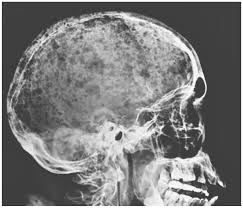

Multiple myeloma is a cancer of plasma cells, which are white blood cells found mainly in the bone marrow. Find more information on clinical trials that are open for enrollment at mount sinai's center for excellence for multiple myeloma. Multiple myeloma (mm), also known as plasma cell myeloma and simply myeloma, is a cancer of plasma cells, a type of white blood cell that normally produces antibodies. Treatment response, detection of relapse. Related online courses on physioplus. 16,000 new cases and 11,000 deaths. Changing the treatment landscape for hematologic malignancies learn more. In multiple myeloma, when the cancer protein level is up, the normal antibody levels are down. If you still can't find it, please let us know so we can add it!. Tell the radiologist or the radiology technician about your diagnosis before receiving dye injection into. It accounts for approximately 10% of all. Other tests include blood monoclonal immunoglobulin and radiology tests to determine the extent of bone lesions. Spotlight revised international staging system for multiple myeloma:

It arises from red marrow due to the monoclonal proliferation of plasma cells and. Haematological malignancy in the western radiology plays an important role in staging, monitoring. Learn more about the symptoms, causes, diagnosis, risk factors, and treatment of multiple myeloma. It accounts for approximately 10% of all. } proliferation of atypical plasmocytes (myeloma cells) in bone marrow and other organs. Multiple myeloma is cancer that starts in the bone marrow's plasma cells. If you still can't find it, please let us know so we can add it!. International myeloma working group molecular classification of multiple myeloma:

Multiple myeloma is a monoclonal gammopathy and is the most common primary malignant bone neoplasm in adults. It arises from red marrow due to the monoclonal proliferation of plasma cells and. Healthy plasma cells help you fight infections by making antibodies that recognize and attack germs. Multiple myeloma (mm), also known as plasma cell myeloma and simply myeloma, is a cancer of plasma cells, a type of white blood cell that normally produces antibodies. A report from international myeloma.